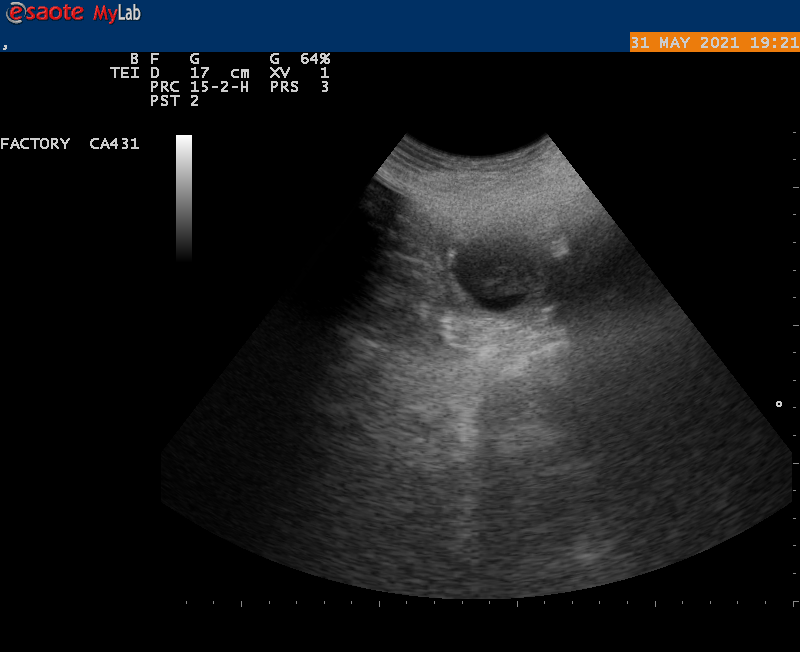

MAANDAG 31 MEI hebben we de echo laten maken, dit is de 30 ste dag van de dekking.

en YES onze Airen is drachtig je kon duidelijk verschillende vruchtblaasjes zien,

welke in de komende weken zullen uitgroeien tot newfy beertjes,